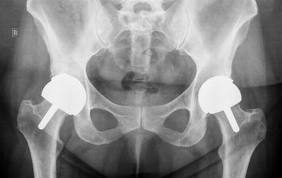

I have been in constant pain since THR surgeries in 2008! My surgeon just pats himself on the back every time he takes follow-up x-rays, saying what a GREAT job he did!

I have to agree – I had my Smith & Nephew THA in August 2003 – and have had constant pain ever since as I have reported – and I am having my 3 year old MoM hip replaced 1 September with a Zimmer ceramic on ceramic.

I am 4 months out of a a revision. I had a S&N resurfacing done in 2007. I spent the summer with respiratory problems and no one could find the answer, My leg with the device began to go numb. I went back to the surgeon who suspected fluid build up in the hip joint and surrounding area. Had an MRI blood work and an aspiration of the joint. The aspiration confirmed the fluid in the joint. The blood work came back with elevated chromium and cobalt levels. They scheduled the surgery for 1 week later to remove the S&N resurfacing had to do a total hip with ceramic and plastic. I ended up at an allergy and asthma specialist. They seemed to think the asthma and the metalosis could be related.